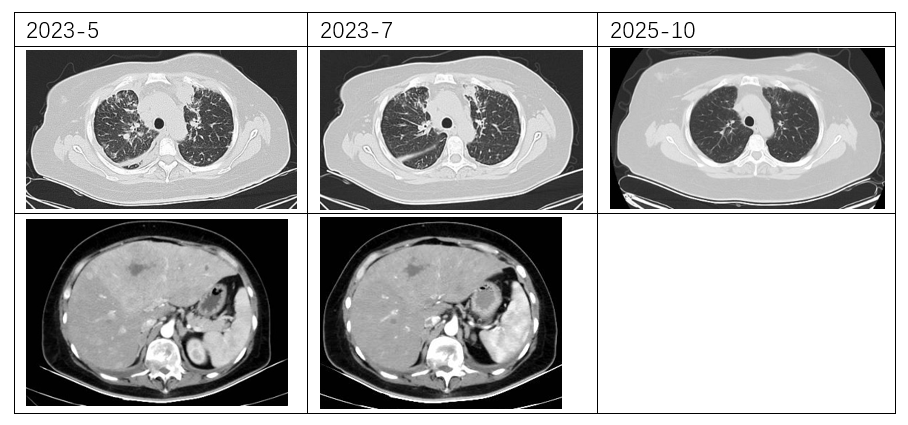

影像学检查:

超声(2023-5基线):左乳11点见低回声占位,约3.1cm×2.6cm,边界不清、形态不规则,内见丰富血流信号,BI-RADS 6类;右乳片状低回声区,建议密切观察。双锁骨上区见低回声占位(左侧约1.8cm×1.5cm,右侧约2.4cm×1.1cm),左腋下见2.1cm×0.9cm低回声淋巴结,均考虑转移。肝体积增大、回声欠均匀,内见多发稍高回声占位(部分内见无回声区),较大约7.3cm×5.1cm,边界不清,考虑转移。

胸部CT(2023-5基线):双肺见多发结节(较大者约7mm×7mm),考虑转移;另见多发类结节影(较大者约27mm×26mm,内可疑支气管气象),需鉴别转移或实变。双肺轴心间质增厚,伴多发小叶间隔增厚,符合癌性淋巴管炎表现。双侧胸膜增厚、胸腔积液,考虑转移。双侧锁骨上区、纵隔多组、双侧内乳区、左腋下及腹膜后见多发肿大淋巴结(较大者约20mm×11mm),考虑转移。胸廓骨多发转移;T2、T12椎体压缩骨折。左乳结节约34mm×19mm,考虑恶性。

腹部CT(2023-5基线):肝脏体积增大,实质内弥漫多发稍低密度结节/肿物(部分可疑融合),较大约121mm×96mm,内见低密度坏死区;增强扫描动脉期高强化,门脉期强化稍减低,考虑转移。肝右后叶下方见11mm×10mm软组织密度结节,脾内见36mm×30mm稍低强化肿物(边界均不清),均考虑转移。双侧肾上腺不均匀增粗,伴15mm×8mm低强化结节,转移可能大。右肾微小囊肿。胆囊、胰腺、左肾未见异常。膀胱部分充盈,壁无明显增厚。左侧附件区形态饱满、强化欠均匀,转移待除外;子宫及右侧附件区未见异常。肝门区及腹膜后见26mm×17mm肿大淋巴结,考虑转移。腹腔、双侧髂血管旁及腹股沟区无肿大淋巴结,无腹盆积液。

疾病转归:

治疗仅8周后,复查胸CT、腹盆CT、头MR、肿瘤标志物,评效结果为缩小的SD,肿瘤标志物下降,肝功能恢复正常。基线27mm的肺部病灶在持续治疗中不断缩小,至2025年4月CT复查完全消失,并维持至今。脑转移灶5mm缩小至2-3mm。

复查胸部CT、腹盆CT、颅内MR、肿瘤标志物显示,疾病至今未进展。治疗不良反应为白细胞及中性粒下降1-2度,停药期间可恢复,无药物剂量调整。